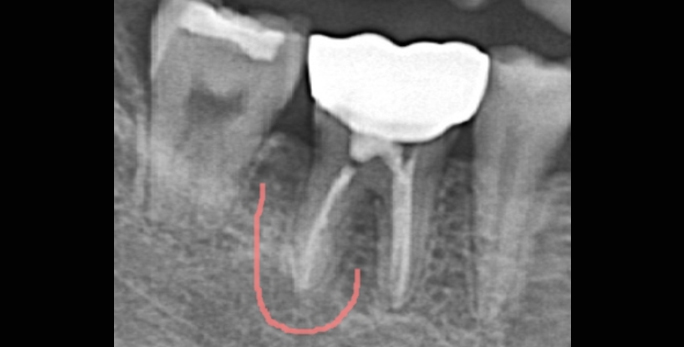

• 심한 치수염으로 타원에서 뿌리뼈 소실로 발치평가 받은 환자 본원에서 치료 후 2개월(깨끗하게 골회복)